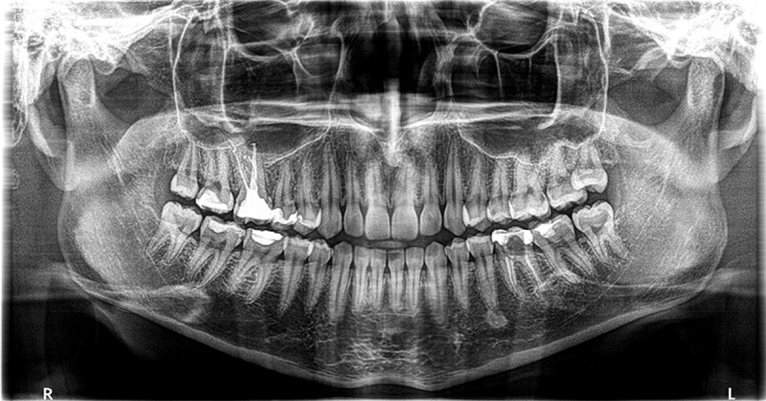

Zahvaljujući naprednoj CBCT (kompjuterska tomografija s konusnim zrakama) tehnologiji u samo 30 sekundi napravit ćemo trodimenzionalni snimak vaših zubnih struktura.

Naš ortopan prikladan je za sve generacije pa tako i za djecu